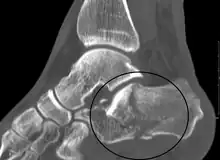

![]() | |

| X-ray of a fractured calcaneus | |